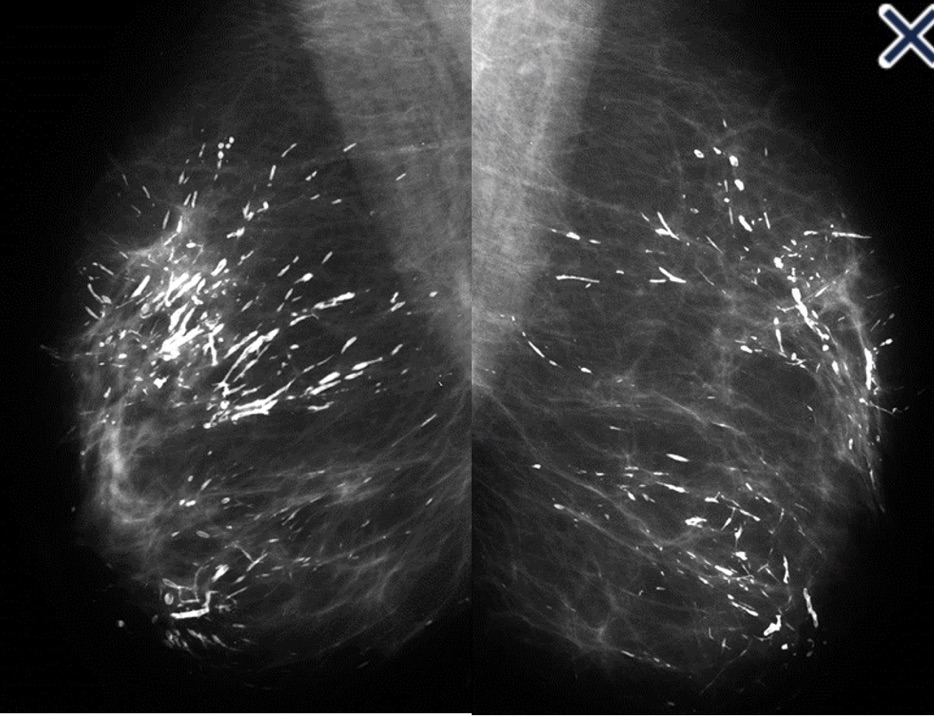

• When coarse rod-like ductal calcifications are diffuse, bilateral, and not confined to a single lobe:

• They can be confidently assumed to result from plasma cell mastitis, and do not require further evaluation or biopsy (Image)

• The process is called secretory disease:

• Because there is a stagnant, viscous fluid that eventually petrifies and results in the smooth contoured calcifications

• Some of them are branching and look like malignant casting type calcifications:

• But the key distinguishing feature is the diffuse, multilobe, bilateral nature of the process:

• Calcifications become much more worrisome when they are confined to a single lobe